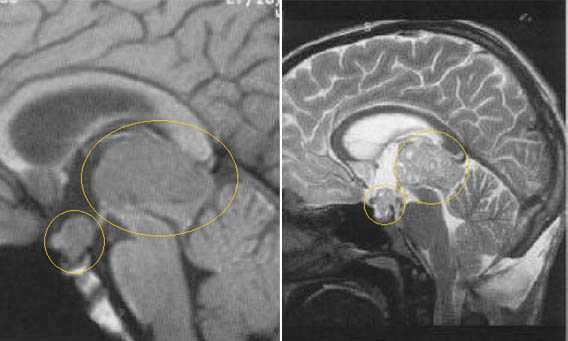

Герминативноклеточный опухоли эпифиза могут метастазировать в другие области. В некоторых случаях герминомы распространяются в область турецкого седла, проявляясь симтоматикой опухолей гипофиза.

Герминома пинеальной области с метастазированием в хиазмально-селлярную область.

Герминома подкорковых образований слева. Мультикистозного строения опухоль с признаками окклюзии отверстия Монро слева.